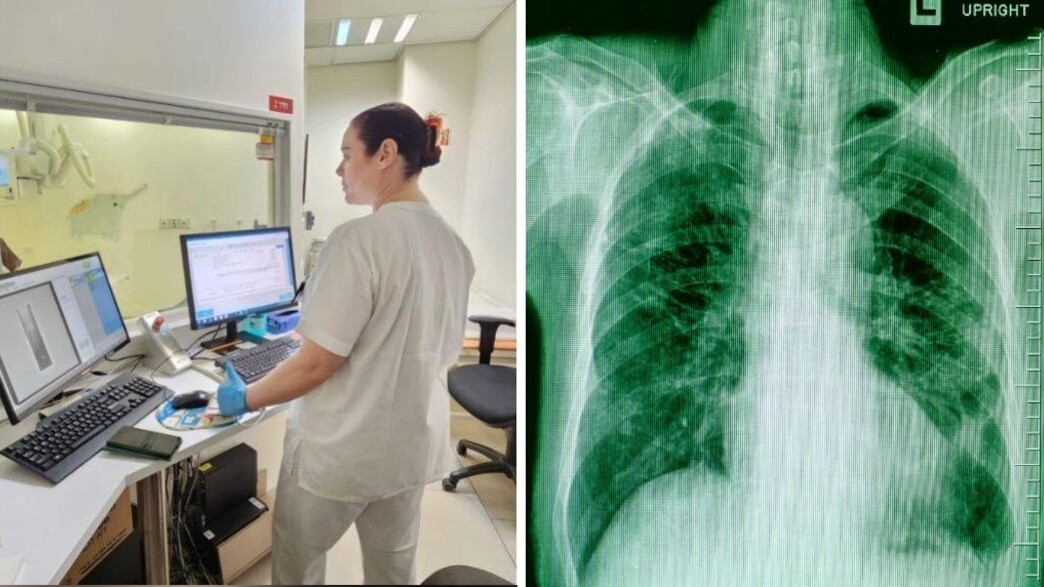

נער בן 18 הגיע לצילום חזה במכון הרנטגן ב"מרכז הרפואי אשדוד יועצת" של כללית, בעקבות כאבים בזמן נשימה ותחושת "חרחורים". למרות שהנער נראה רגוע ולא הראה סימני מצוקה, הצילום גילה מציאות מסוכנת הרבה יותר .

אילנית ביטל, הדימותנית שביצעה את הצילום, זיהתה מיד ממצא מסוכן. "כשהסתכלתי על הצילום ראיתי שמדובר בחזה אוויר (פניאומוטורקס) גדול בצד ימין, שהוא מצב שעלול לסכן חיים", היא מספרת. "ביקשתי מהנער שלא לזוז מהמקום עד קבלת אישור רפואי ובמקביל יצרתי מיד קשר עם ד"ר בועז שילוני, הרדיולוג המחוזי, שקבע תוך דקות כי מדובר במקרה חמור הדורש התערבות רפואית מיידית ופינוי לבית החולים".

מהו חזה אוויר (פניאומוטורקס)?

חזה אוויר הוא מצב רפואי שבו מצטבר אוויר בחלל שבין הריאה לדופן בית החזה, לרוב כתוצאה מקרע או פציעה בריאה.האוויר הלכוד לוחץ על הריאה ועלול לגרום לה לקרוס חלקית או לחלוטין. זהו מצב חירום רפואי, שיכול להחמיר במהירות ולגרום למצוקה נשימתית ואף לסכנת חיים אם לא מטופל בהקדם.